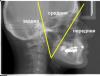

kirovsasa Опубликовано 6 мая, 2010 Автор Поделиться Опубликовано 6 мая, 2010 Вопрос по ТРГ. Я тренировался в анализе по Кларку , углы не пошли (квадрат кривой нарисовал, и лишняя линия там есть) , буду переделывать. Я правильно точки поставил?Где то упустил описание оси мыщелка, где точки этой оси (одна центр суставной головки, а вторая)?Если на ТРГ два контура ветви н.ч. , то какая из них расчётная (это уже не к Кларку, а для общего развития)? http://i055.radikal.ru/1005/61/a7e591764d2a.jpg Ссылка на комментарий

Skip Опубликовано 8 мая, 2010 Поделиться Опубликовано 8 мая, 2010 Вопрос по ТРГ. Я тренировался в анализе по Кларку , углы не пошли (квадрат кривой нарисовал, и лишняя линия там есть) , буду переделывать. Я правильно точки поставил?Почему Вы негативы выкладываете, там же ничего разглядеть невозможно? А говоря вообщем, я бы посоветовал начать изучение ТРГ не с какого-то конкретного авторского анализа, а с изучения рентгеноанатомии скелетных ориентиров. Книг полно на эту тему, обязательно найдите... Где то упустил описание оси мыщелка, где точки этой оси (одна центр суставной головки, а вторая)?Ну а это нафига Вам нужно..? Если на ТРГ два контура ветви н.ч. , то какая из них расчётная (это уже не к Кларку, а для общего развития)?Среднее значение берите, между линиями... Ссылка на комментарий

kirovsasa Опубликовано 8 мая, 2010 Автор Поделиться Опубликовано 8 мая, 2010 Кларк выделяет три параллельные линии в вертикальной плоскости (при гармонии) ось в. резцов, лицевая ось, ось мыщелка. При этом результат лечения будет стабильным. А как проводить ось мыщелка я пока не нашёл, так надо? http://s56.radikal.ru/i152/1005/90/0f38377d48cd.jpg Ссылка на комментарий